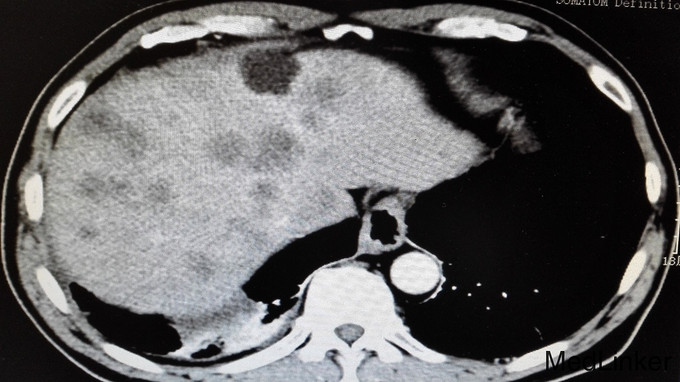

体格检查无特殊,未见明显阳性体征。 进一步完善辅助检查: 尿常规、大便常规、胸片、肝肾功能、血糖、血沉、风湿三项大致正常。血常规:白细胞11.7 ×10 9/L。右小腿MRI:1、右踝周围软组织信号改变,考虑炎症,请结合临床,必要时增强检查。2、右踝关节腔少许积液。血常规、心肌酶、电解质正常,心电图、心脏彩超未见明显异常。腹部CT平扫:1、肝实质多发稍低密度影性质待定,考虑转移瘤,建议进一步检查。2、肝左叶、尾叶多发低密度影性质待定,考虑囊肿。3、胆囊摘除术后。4、主动脉及右冠状动脉局部管壁钙化。AFP、CA199正常,CEA:6256.85ng/ml。输血前四项全阴性。全腹部增强CT提示:1、胃窦壁增厚,肝实质多发稍低密度影,考虑胃CA并肝内转移瘤可能,建议胃镜检查。2、肝左叶、尾叶多发囊肿。3、胆囊摘除术后。4、左肾囊肿。5、右肺下叶感染;左肺下叶纤维化病灶。6、主动脉及右冠状动脉局部管壁钙化。行胃肠镜检查提示慢性浅表性胃炎和盲肠占位,占位大小约40mm,已取病检。病检结果提示:盲肠中分化腺癌。

诊断:1、盲肠中分化腺癌并肝脏多发转移;2、右小腿软组织感染。 告知患者病情,目前无手术治疗指征,转肿瘤科行以化疗为主的肿瘤综合治疗。 患者经过再三考虑后,转省肿瘤医院消化肿瘤内科继续治疗。